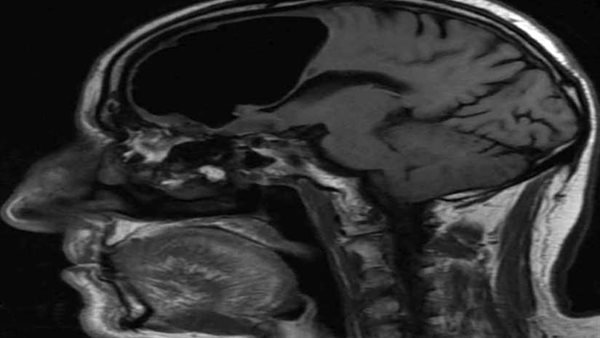

وقالت " روسيا اليوم: "اكتشف الأطباء وجود "تجويف هوائي" يبلغ طوله 10 سنتيمترات في النصف الأيمن من دماغ رجل مسن نقل إلى المستشفى عقب شعوره بالدوار وسقوطه على الأرض، بعد أن تبددت شكوكهم بإصابته بسكتة دماغية.

وبينت نتائج التصوير بالرنين المغناطيسي لدماغ الرجل المسن، وجود ما يسمى بالفتق الهوائي وهو ما يلاحظ عادة لدى المرضى الذين يعانون من إصابات في أجزاء معيّنة من الجسم والأعضاء الداخلية.

كما كشف الفحص وجود ورم عظمي "تشكّل حميد في عظام الوجه يفصل بين تجويف الأنف والدماغ"، دخل من خلاله الهواء إلى دماغ الرجل وبقي فيه لعقود من الزمن، ما أدى إلى الضغط على الدماغ وتعطيل التنسيق في بعض وظائفه الحيوية، وهذا ما أدى إلى شكوى الرجل من الدوار المتكرر.